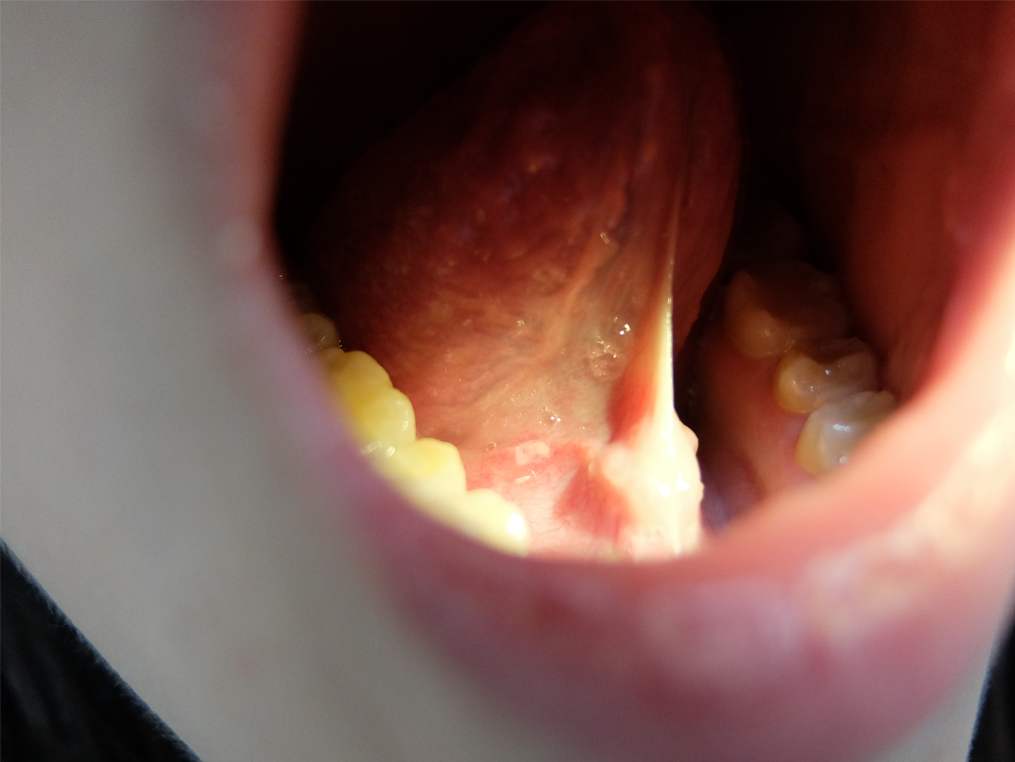

베체트병.png

면역결핍.png

(왼쪽부터) 베체트병, 소아면역결핍 이미지 / 출처: 대한소아임상면역학회